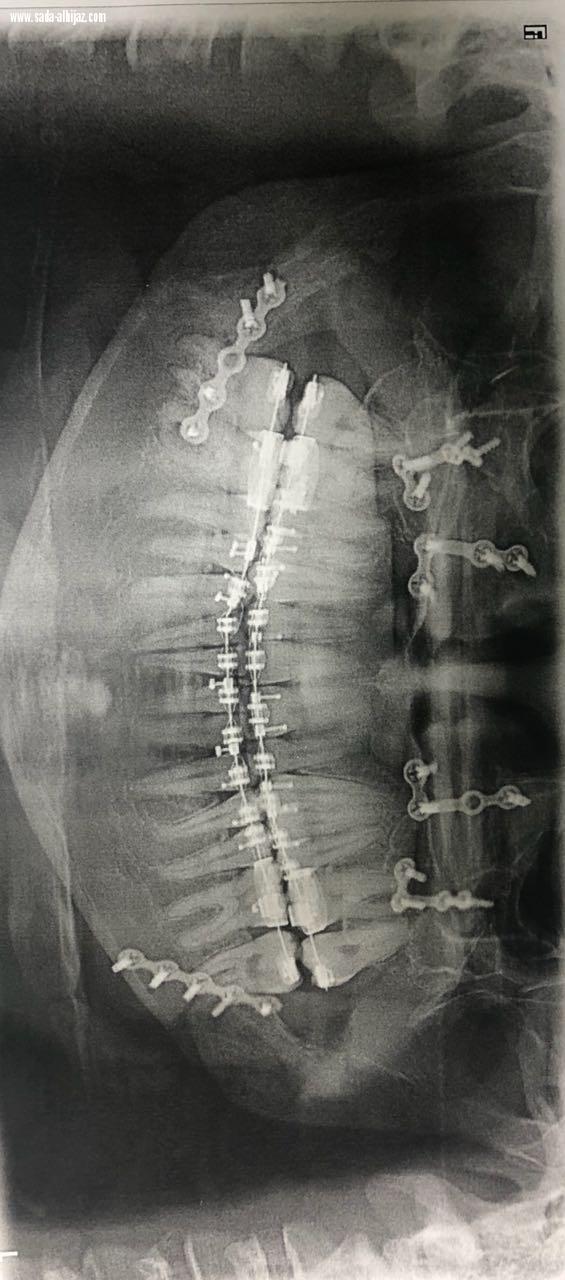

وأضاف د. البلوي بعد ذلك تم عمل إجراء جراحي على نموذج تم عمله في معمل طب وجراحة الأسنان بالمستشفى قبل البدء بالعمليه فعلياً وبعد الإنتهاء من كافة الفحوصات اللازمة تم إجراء العملية للمريض وهي عبارة عن تقديم الفك العلوي بمقدار 2 ملم، وارجاع الفك السفلي بمقدار 4 ملم مع التدوير إلى جهة اليسار لإصلاح خط المنتصف تكللت بالنجاح ولله الحمد.

وتعتبر هذه العملية السابعة من نوعها بعد إجراء ست عمليات في الفتره الماضيه لأربع سيدات عانين من هذه المشكله جميعها تكللت بالنجاح مع العلم بأن هذا الإجراء إلى مهاره عالية ودقيقة وخبره طويله في جراحة الوجه والفكين التقويمية وبرامج معقده.